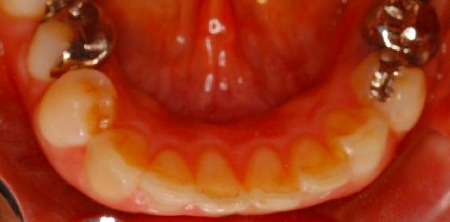

8ヶ月後の終了時

これが可能なのは、いくつかの条件がそろった状態で、一本単位ではなく何本かまとめて動かしたからです。